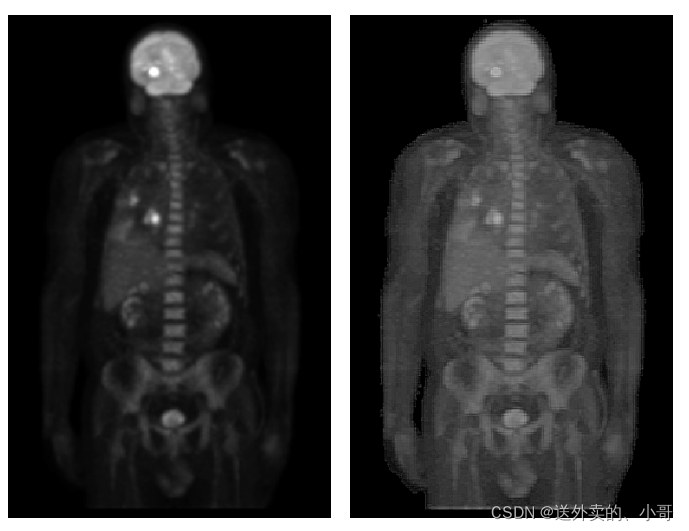

测试结果: